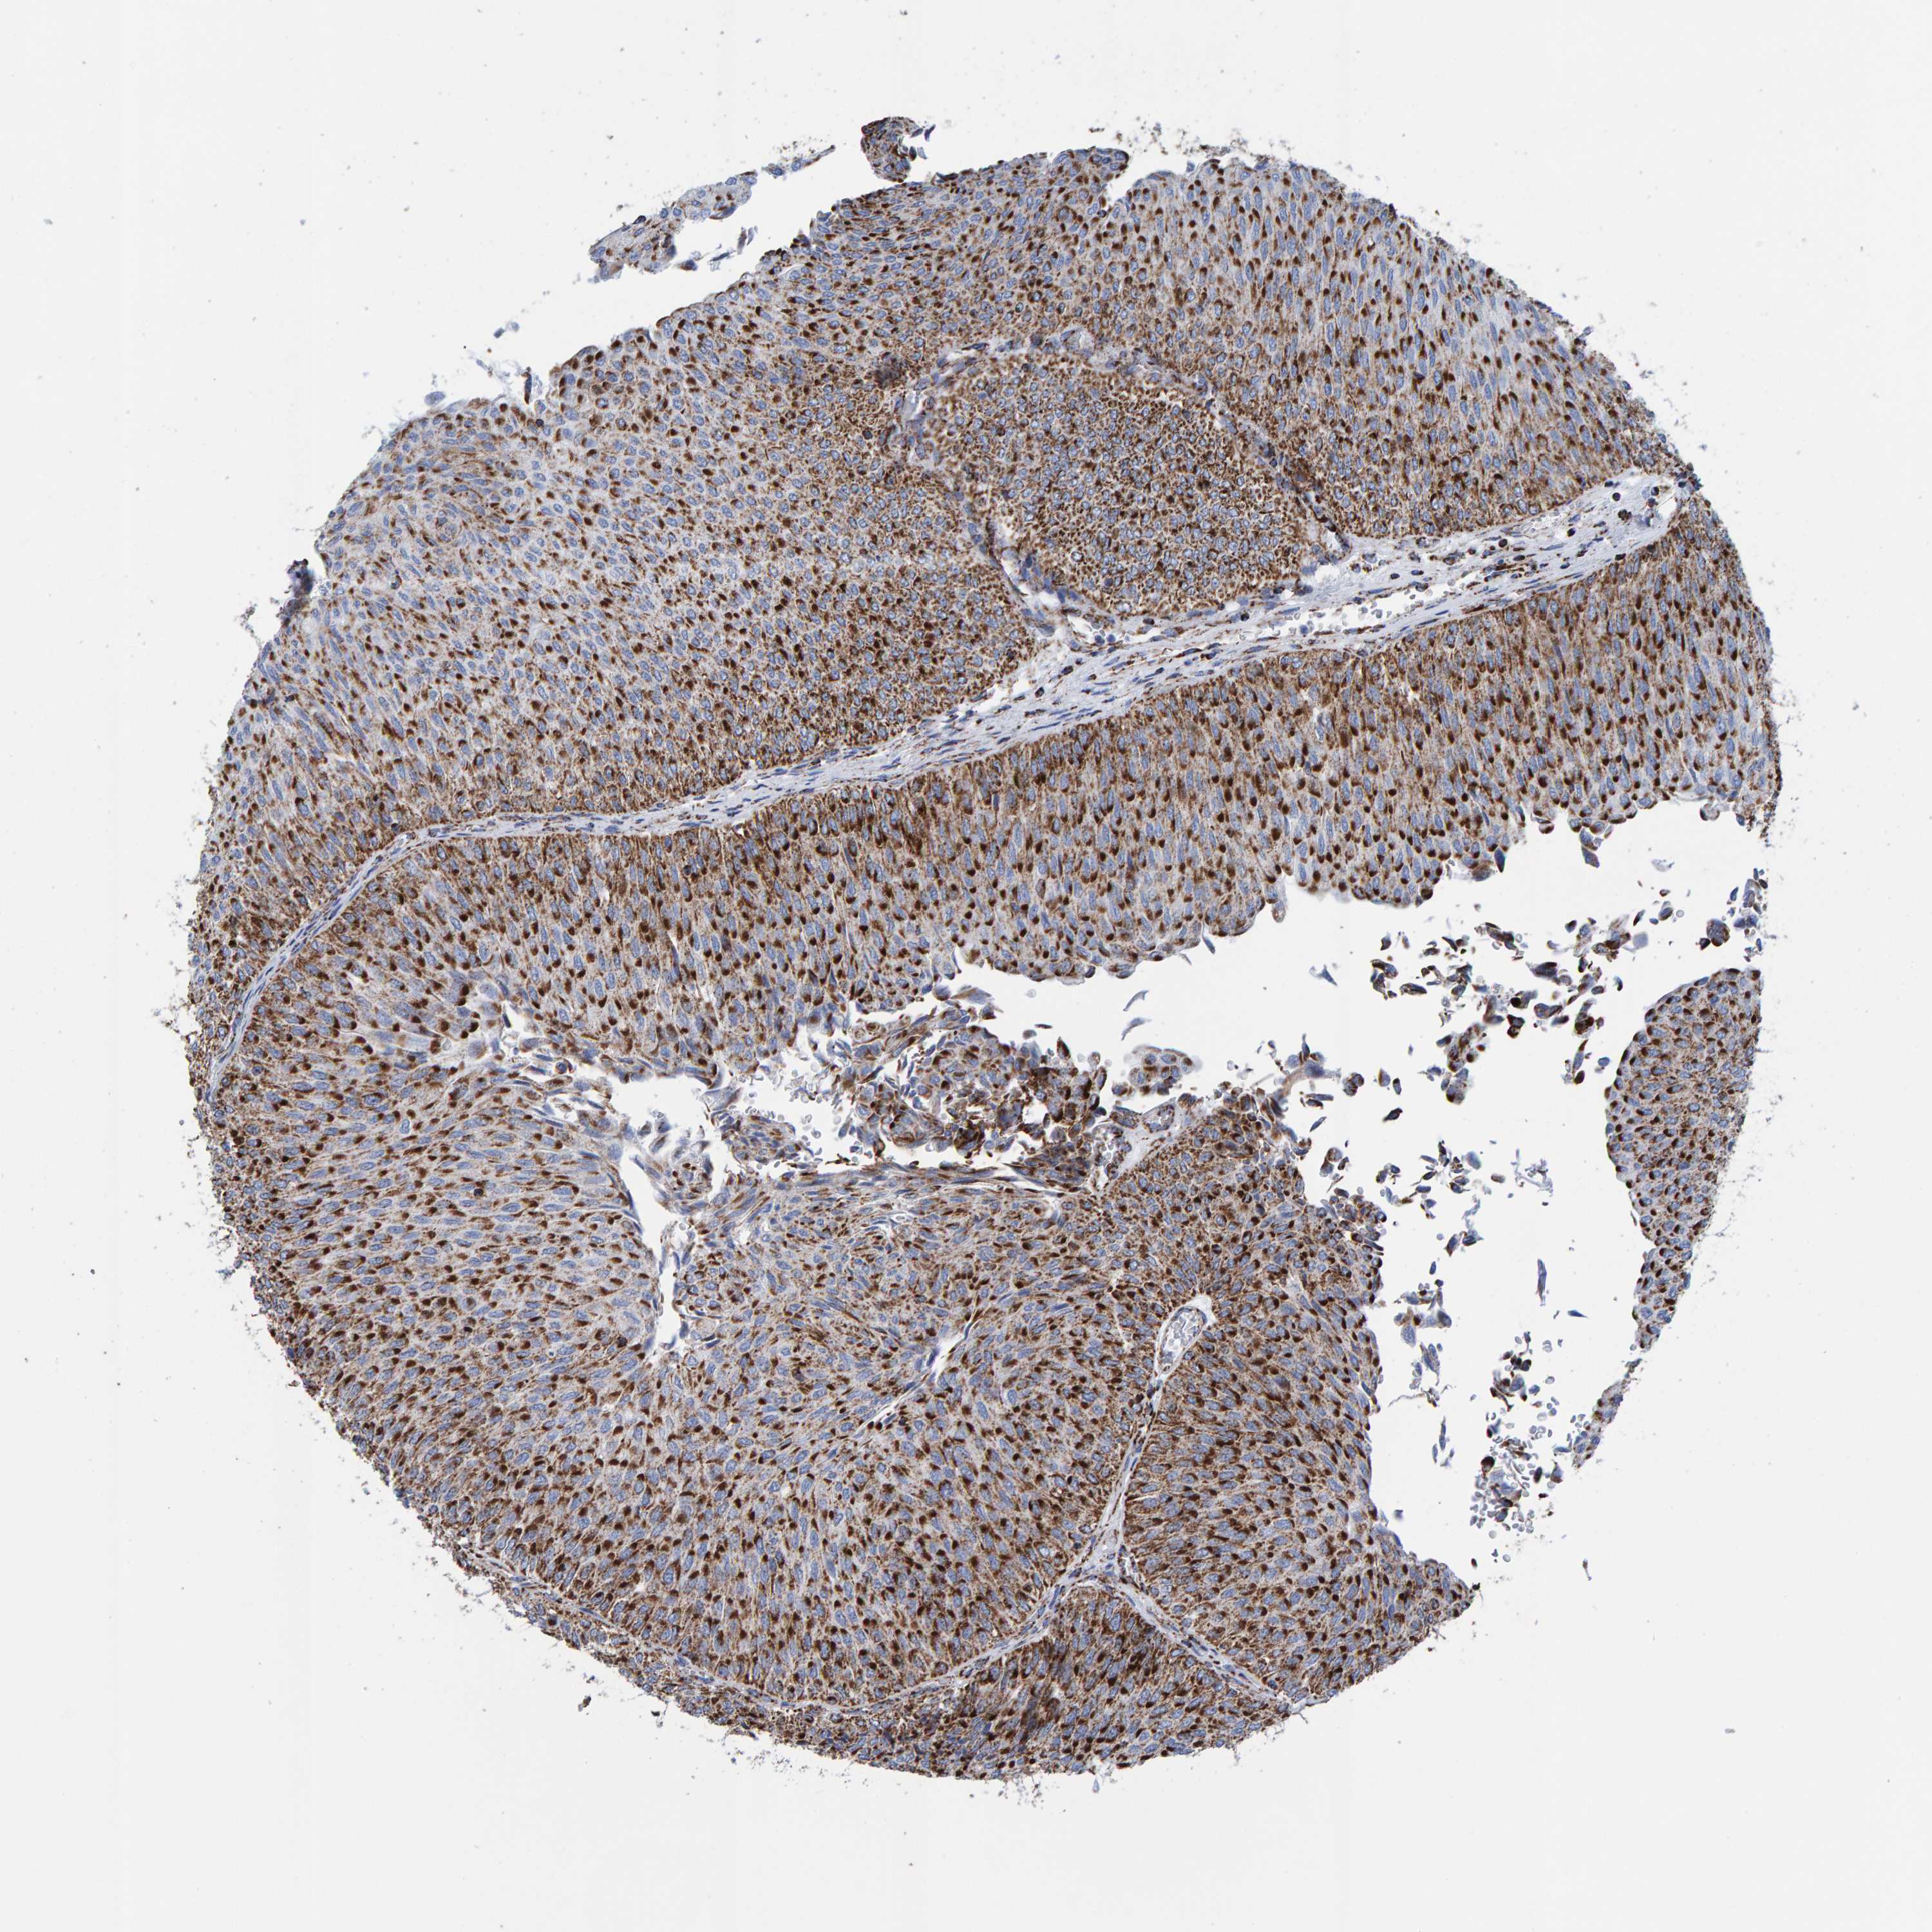

UROTHELIAL CANCER - Protein expressioni

A mouse-over function shows sample information and annotation data. Click on an image to view it in a full screen mode. Samples can be filtered based on level of antibody staining by selecting one or several of the following categories: high, medium, low and not detected. The assay and annotation is described here.

Note that samples used for immunohistochemistry by the Human Protein Atlas do not correspond to samples in the TCGA dataset.

Antibody stainingi

Antibody staining in the annotated cell types in the current human tissue is reported as not detected, low, medium, or high, based on conventional immunohistochemistry profiling in selected tissues. This score is based on the combination of the staining intensity and fraction of stained cells.

Each image is clickable and will lead to virtual microscopy that enables deeper exploration of all samples and also displays staining intensity scores, fraction scores and subcellular localization as well as patient and tissue information for each sample.

Antibody HPA022853

Antibody HPA023043

Antibody HPA023048

Staining

High

Medium

Low

Not detected

Intensity

Strong

Moderate

Weak

Negative

Quantity

>75%

75%-25%

<25%

None

Location

Nuclear

Cytoplasmic/membranous

Cytoplasmic/membranous,nuclear

Urothelial carcinoma, Low grade

Urothelial carcinoma, High grade